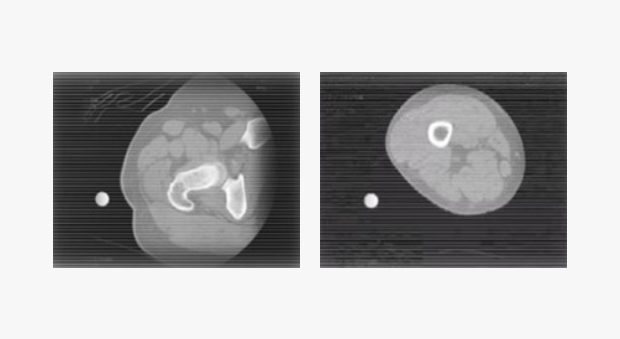

利用 CT 斷層掃描後,依患者的醫療診斷影像,生成每位患者專屬的 3D 骨骼模型,

使醫療團隊可在術前確認骨骼狀態並擬定最適合的手術計劃。

(患者CT影像)